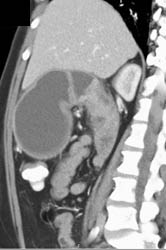

Antral Carcinoma